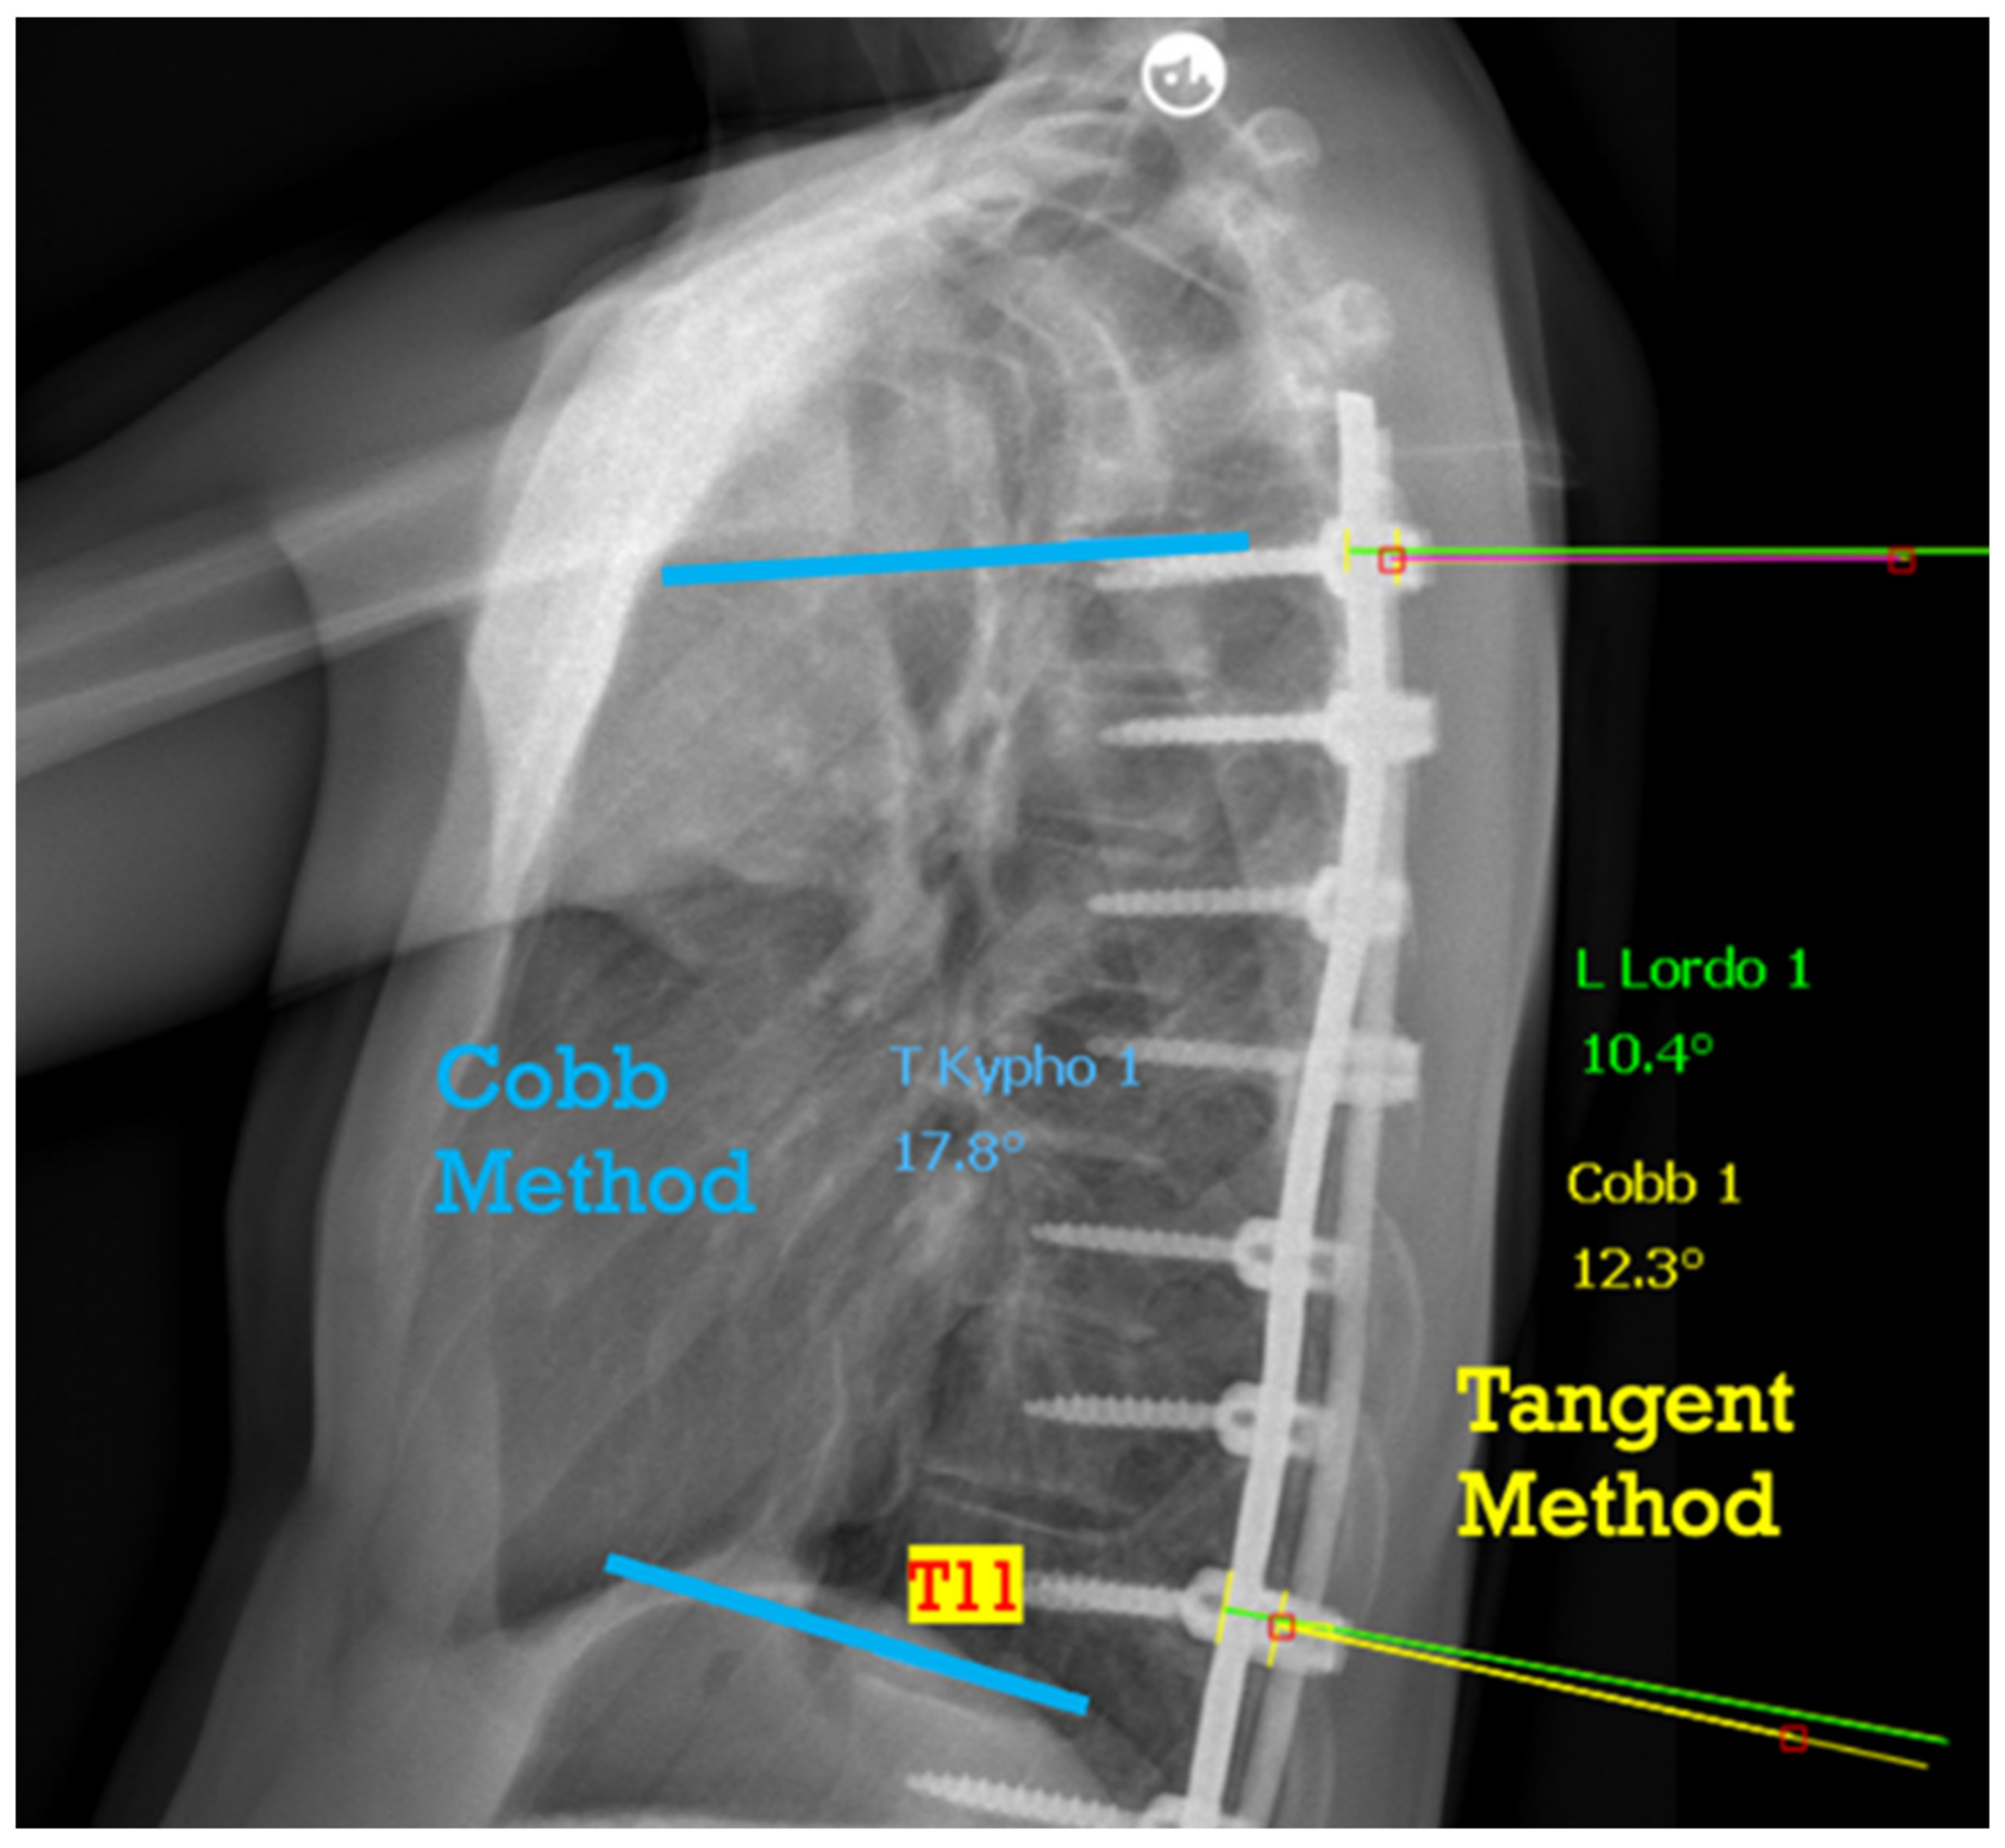

2.3. Data Collection and Radiographic Measurement